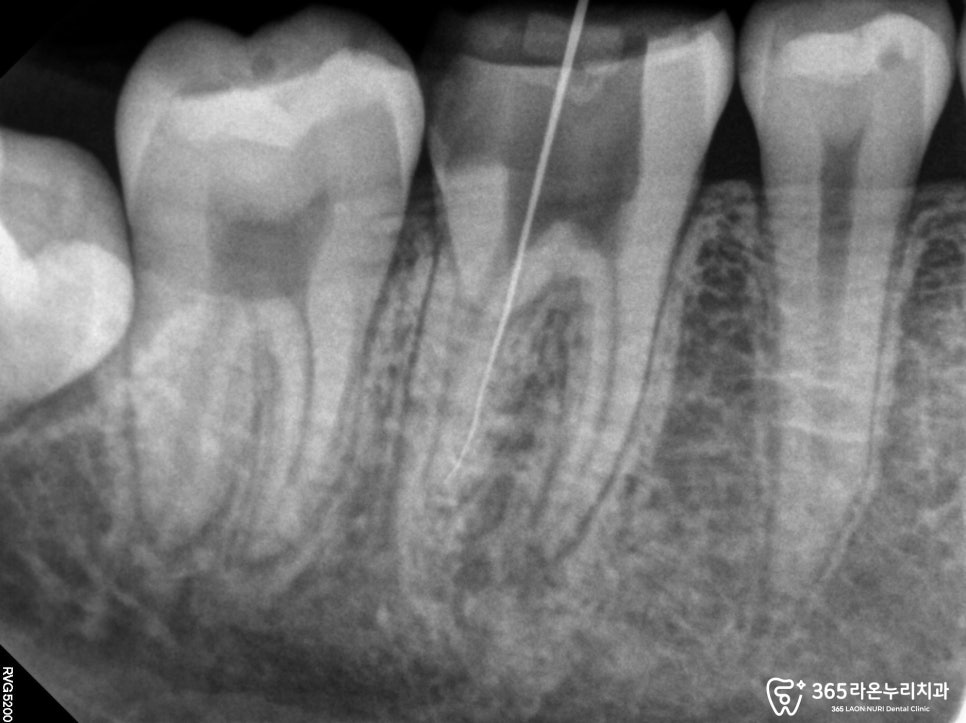

뜨겁고 시린

통증을 느낀 것을 보아

감염이 심했을 것으로 예상되었기 때문에

약 3~4회에 걸친

내부 세척과 소독을 통해

수복까지 잘 마무리했습니다.